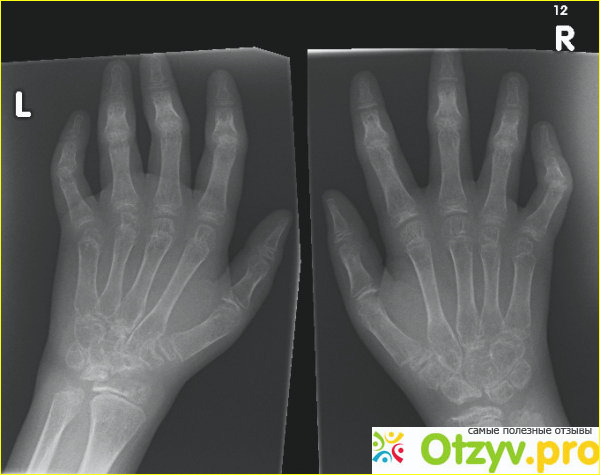

Всем привет. Меня зовут Светлана. Диагноз - ревматоидный артрит кистей - мне поставили три года назад.

Дала о себе знать стирка в холодной воде и проживание в сельской местности. Тяжелый физические нагрузки на руки, когда нужно и копать и сапать, и много всякой другой мелкой работы по дому. Бойлера и газа у нас в доме нет. Посуду приходилось мыть в ледяной воде и стирать тоже. Через какое-то время стала чувствовать к вечеру ноющую, монотонную, жуткую боль в суставах пальцев. Не знала куда приткнуть руки. Заматывала в теплое полотенце, грела у печки, пользовалась разными кремами согревающими, но ничего не давало результата. Боль возвращалась каждый раз в самое неподходящее время. Но к ночи становилось еще хуже... После обращения к врачу и постановки диагноза - ревматоидный артрит - мне назначили физиопроцедуры, таблетки и мази. На время боль снимал Диклофенак. Но долго принимать его не смогла. Так как стала мучить тошнота и боли в желудке. Позже подключила Ибупрофен, так как Диклофенак уже помогал слабее. Но и Ибупрофен тоже долго принимать не смогла - он убирал боль на некоторое время. Но боль возвращалась снова. Да и желудок стал подводить. Терпеть больше не было сил. Чувствовала себя я ужасно. Сил, чтобы работать да и просто - не было. Слабость была во всем теле. Конечно с таким состоянием приходит и депрессия, разбитость. Но самое ужасное - это, конечно, ломота во всех суставах и костях, помимо рук. Ноющие боли в мышцах, которые сохранялись длительное время...